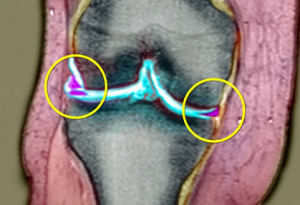

برای تشخیص پارگی منیسک، پزشک و فیزیوتراپیست شما را معاینه کامل می کند و از شما می پرسد که چگونه آسیب دیدید. آنها زانوی شما را بررسی می کنند تا ببینند آیا حساسیتی در امتداد خط مفصلی که منیسک در آن قرار دارد وجود دارد یا خیر. پزشک ممکن است آزمایش های دیگری را نیز تجویز کند. آنها ممکن است برای رد شکستگی استخوان، آرتریت و سایر مشکلات از اشعه ایکس استفاده کنند. آنها همچنین ممکن است MRI را انجام دهند (تصویر شماره ۱) که امکان ارزیابی دقیق تر غضروف و منیسک زانو را فراهم می کند.

تصویرشماره ۱ : پارگی منیسک در MRI (نواحی ارغوانی)